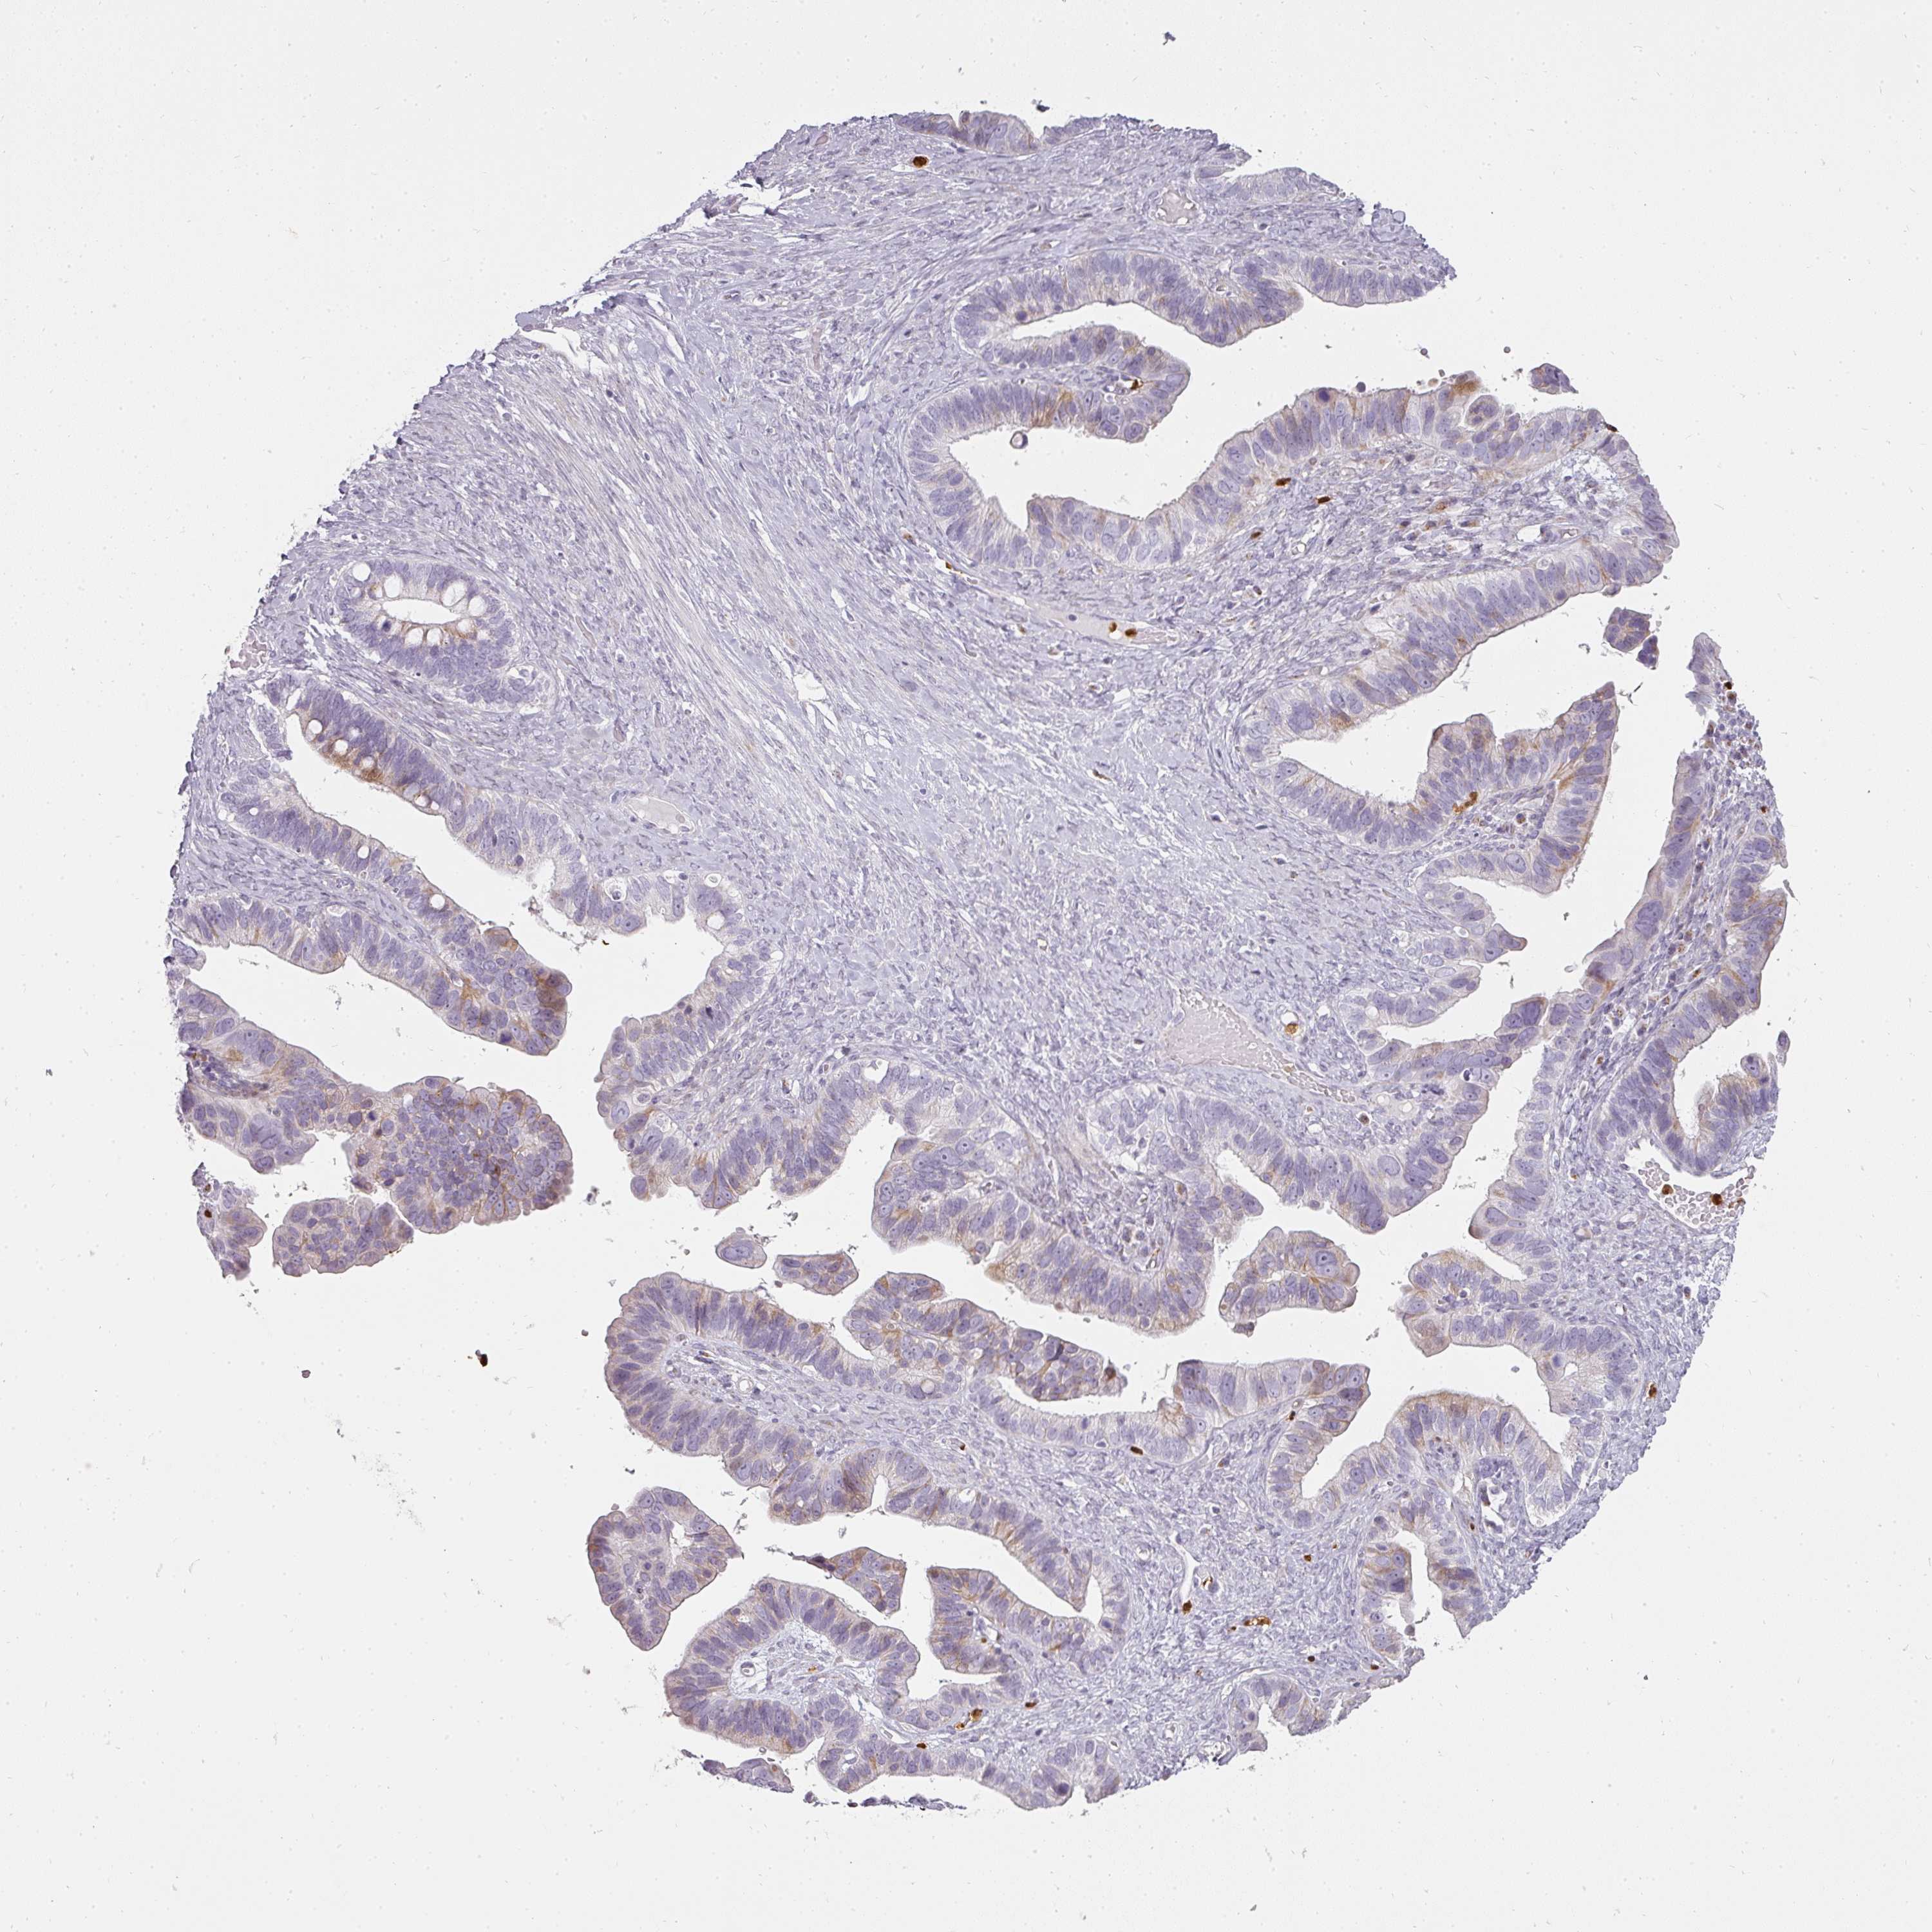

OVARIAN CANCER - Protein expressioni

A mouse-over function shows sample information and annotation data. Click on an image to view it in a full screen mode. Samples can be filtered based on level of antibody staining by selecting one or several of the following categories: high, medium, low and not detected. The assay and annotation is described here.

Note that samples used for immunohistochemistry by the Human Protein Atlas do not correspond to samples in the TCGA dataset.

Antibody stainingi

Antibody staining in the annotated cell types in the current human tissue is reported as not detected, low, medium, or high, based on conventional immunohistochemistry profiling in selected tissues. This score is based on the combination of the staining intensity and fraction of stained cells.

Each image is clickable and will lead to virtual microscopy that enables deeper exploration of all samples and also displays staining intensity scores, fraction scores and subcellular localization as well as patient and tissue information for each sample.

Antibody HPA051360

Staining

Cystadenocarcinoma, serous, NOS

Carcinoma, endometroid

Cystadenocarcinoma, mucinous, NOS

Carcinoma, NOS